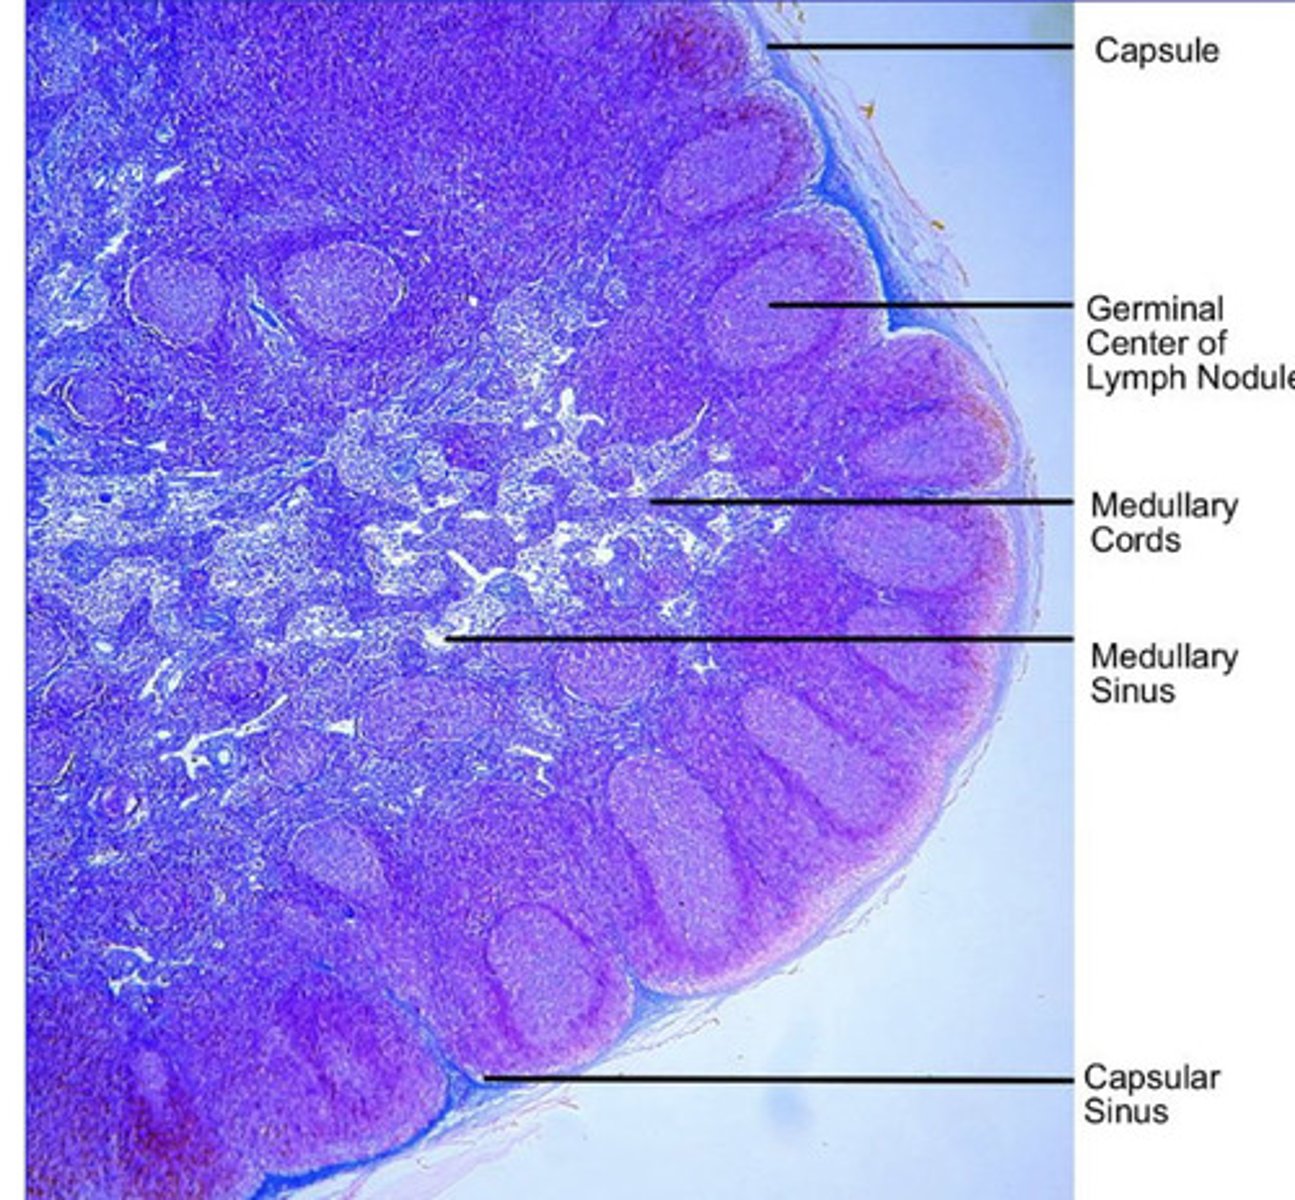

are lymph nodes tubular or parenchymal?

parenchymal-

cortex- follicles with mantle, germinal center, B lymphocytes

medulla- capillaries

what is the structure of lymph nodes?

cortex

what part of the lymph node has follicles with B cells?

interfollicular tissue in the cortex

what part of the lymph node has T cells?